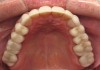

Figure 3 through Figure 7 Preoperative retracted, occlusal, and lingual views. Note the extreme acid erosion, with lost occlusal and lingual enamel.

When viewing his maxillary teeth from an occlusal and lingual view, one can see the erosion and wear (Figure 4, Figure 6, and Figure 7), and it becomes evident just how collapsed he actually is. This patient shows more teeth on his left side and less on the right when smiling, and the shortness and color of his teeth contributes to a definite aging of his smile. Additionally, his lips appear less full without the lip support of the lost tooth structure. The patient had Class I molar relationships on both the right and left sides, and a posterior open bite on his right side in the area of teeth Nos. 4 through 6 (Figure 8 and Figure 9). There was no crowding evident and both arches were found to have lingually inclined teeth, which may have contributed to his wear. It was also noted that his posterior teeth were worn down with a very flat anatomy and lacked proper functional guidance.